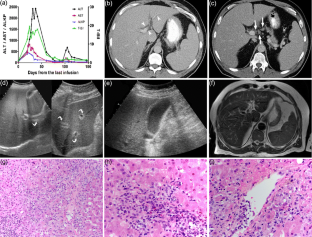

Ipilimumab is a novel immunomodulator demonstrating promising efficacy in treatment of melanoma and other cancers. The clinical benefit from ipilimumab can be hampered by the immure-related adverse events (irAEs) caused by dysregulation of host immune system. Ipilimumab associated hepatitis is also an important irAE, however, there have been limited descriptions of its clinicopathologic and imaging characteristics. We aim to describe the clinicopathologic and imaging characteristics of 6 patients who were diagnosed as ipilimumab associated hepatitis during the ipilimumab treatment for melanoma. The clinical features of these patients were as follows: (1) severe cases with systemic symptoms and highly increased level of liver function tests (LFTs), and (2) mild asymptomatic cases with mildly increased level of LFTs. In severe cases with ALT >1,000 IU/L, imaging findings were characterized by mild hepatomegaly, periportal edema, and periportal lymphadenopathy, while mild cases showed normal imaging findings. This spectrum of imaging findings in our series was similar to that of common causes of acute hepatitis. Among 3 cases with pathologic specimen, two cases showed severe panlobular hepatitis with prominent perivenular infiltrate with endothelialitis, suggestive of predominant injury to hepatocytes, while the other case showed mild portal mononuclear infiltrate around proliferated bile ductules, suggestive of predominant injury to bile ducts. In summary, ipilimumab associated hepatitis may demonstrate variable imaging findings according to its clinical severity, and histologically may manifest either as a predominant injury to hepatocytes (acute hepatitis pattern) or as a predominant injury to bile ducts (biliary pattern).

Fig. 2